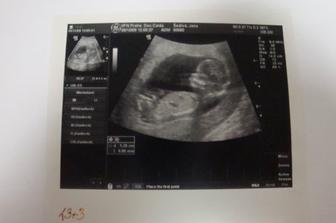

28.12.09 velký UZ s NT screeningem v porodnici u Apolináře - výsledek negativní!!! 🙂)) odpovídáme 13+3tt a fazolka měří 8cm od hlavičky k zadečku